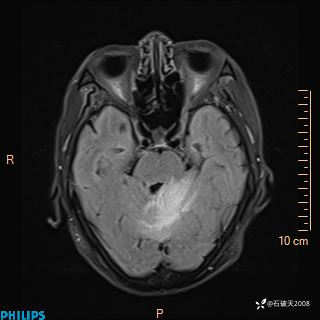

T2

T1